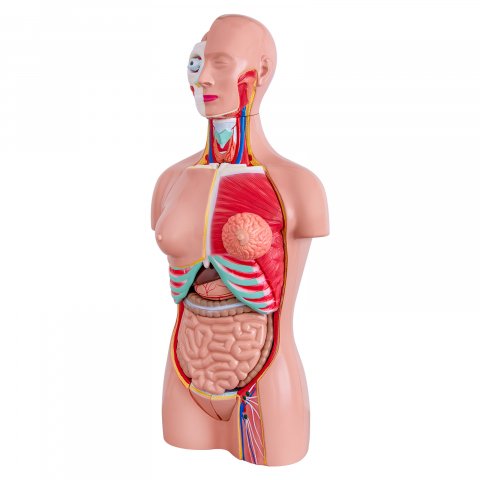

Modelul este conceput din material plastic PVC și este frumos colorat.

Acest model este conceput ca ajutor vizual pentru predarea cursurilor de anatomie umană și igienă. Este folosit pentru a demonstra structura dintelui, la studiul sistemului digestiv în gimnaziu, liceu și școli postliceale medicale.

Acest model are înălțimea de 23-26 cm, prezintă 3 rădăcini, o secțiune longitudinală prin care se poate observa structura interioara a dintelui, este conceput din material plastic PVC și este frumos colorat.